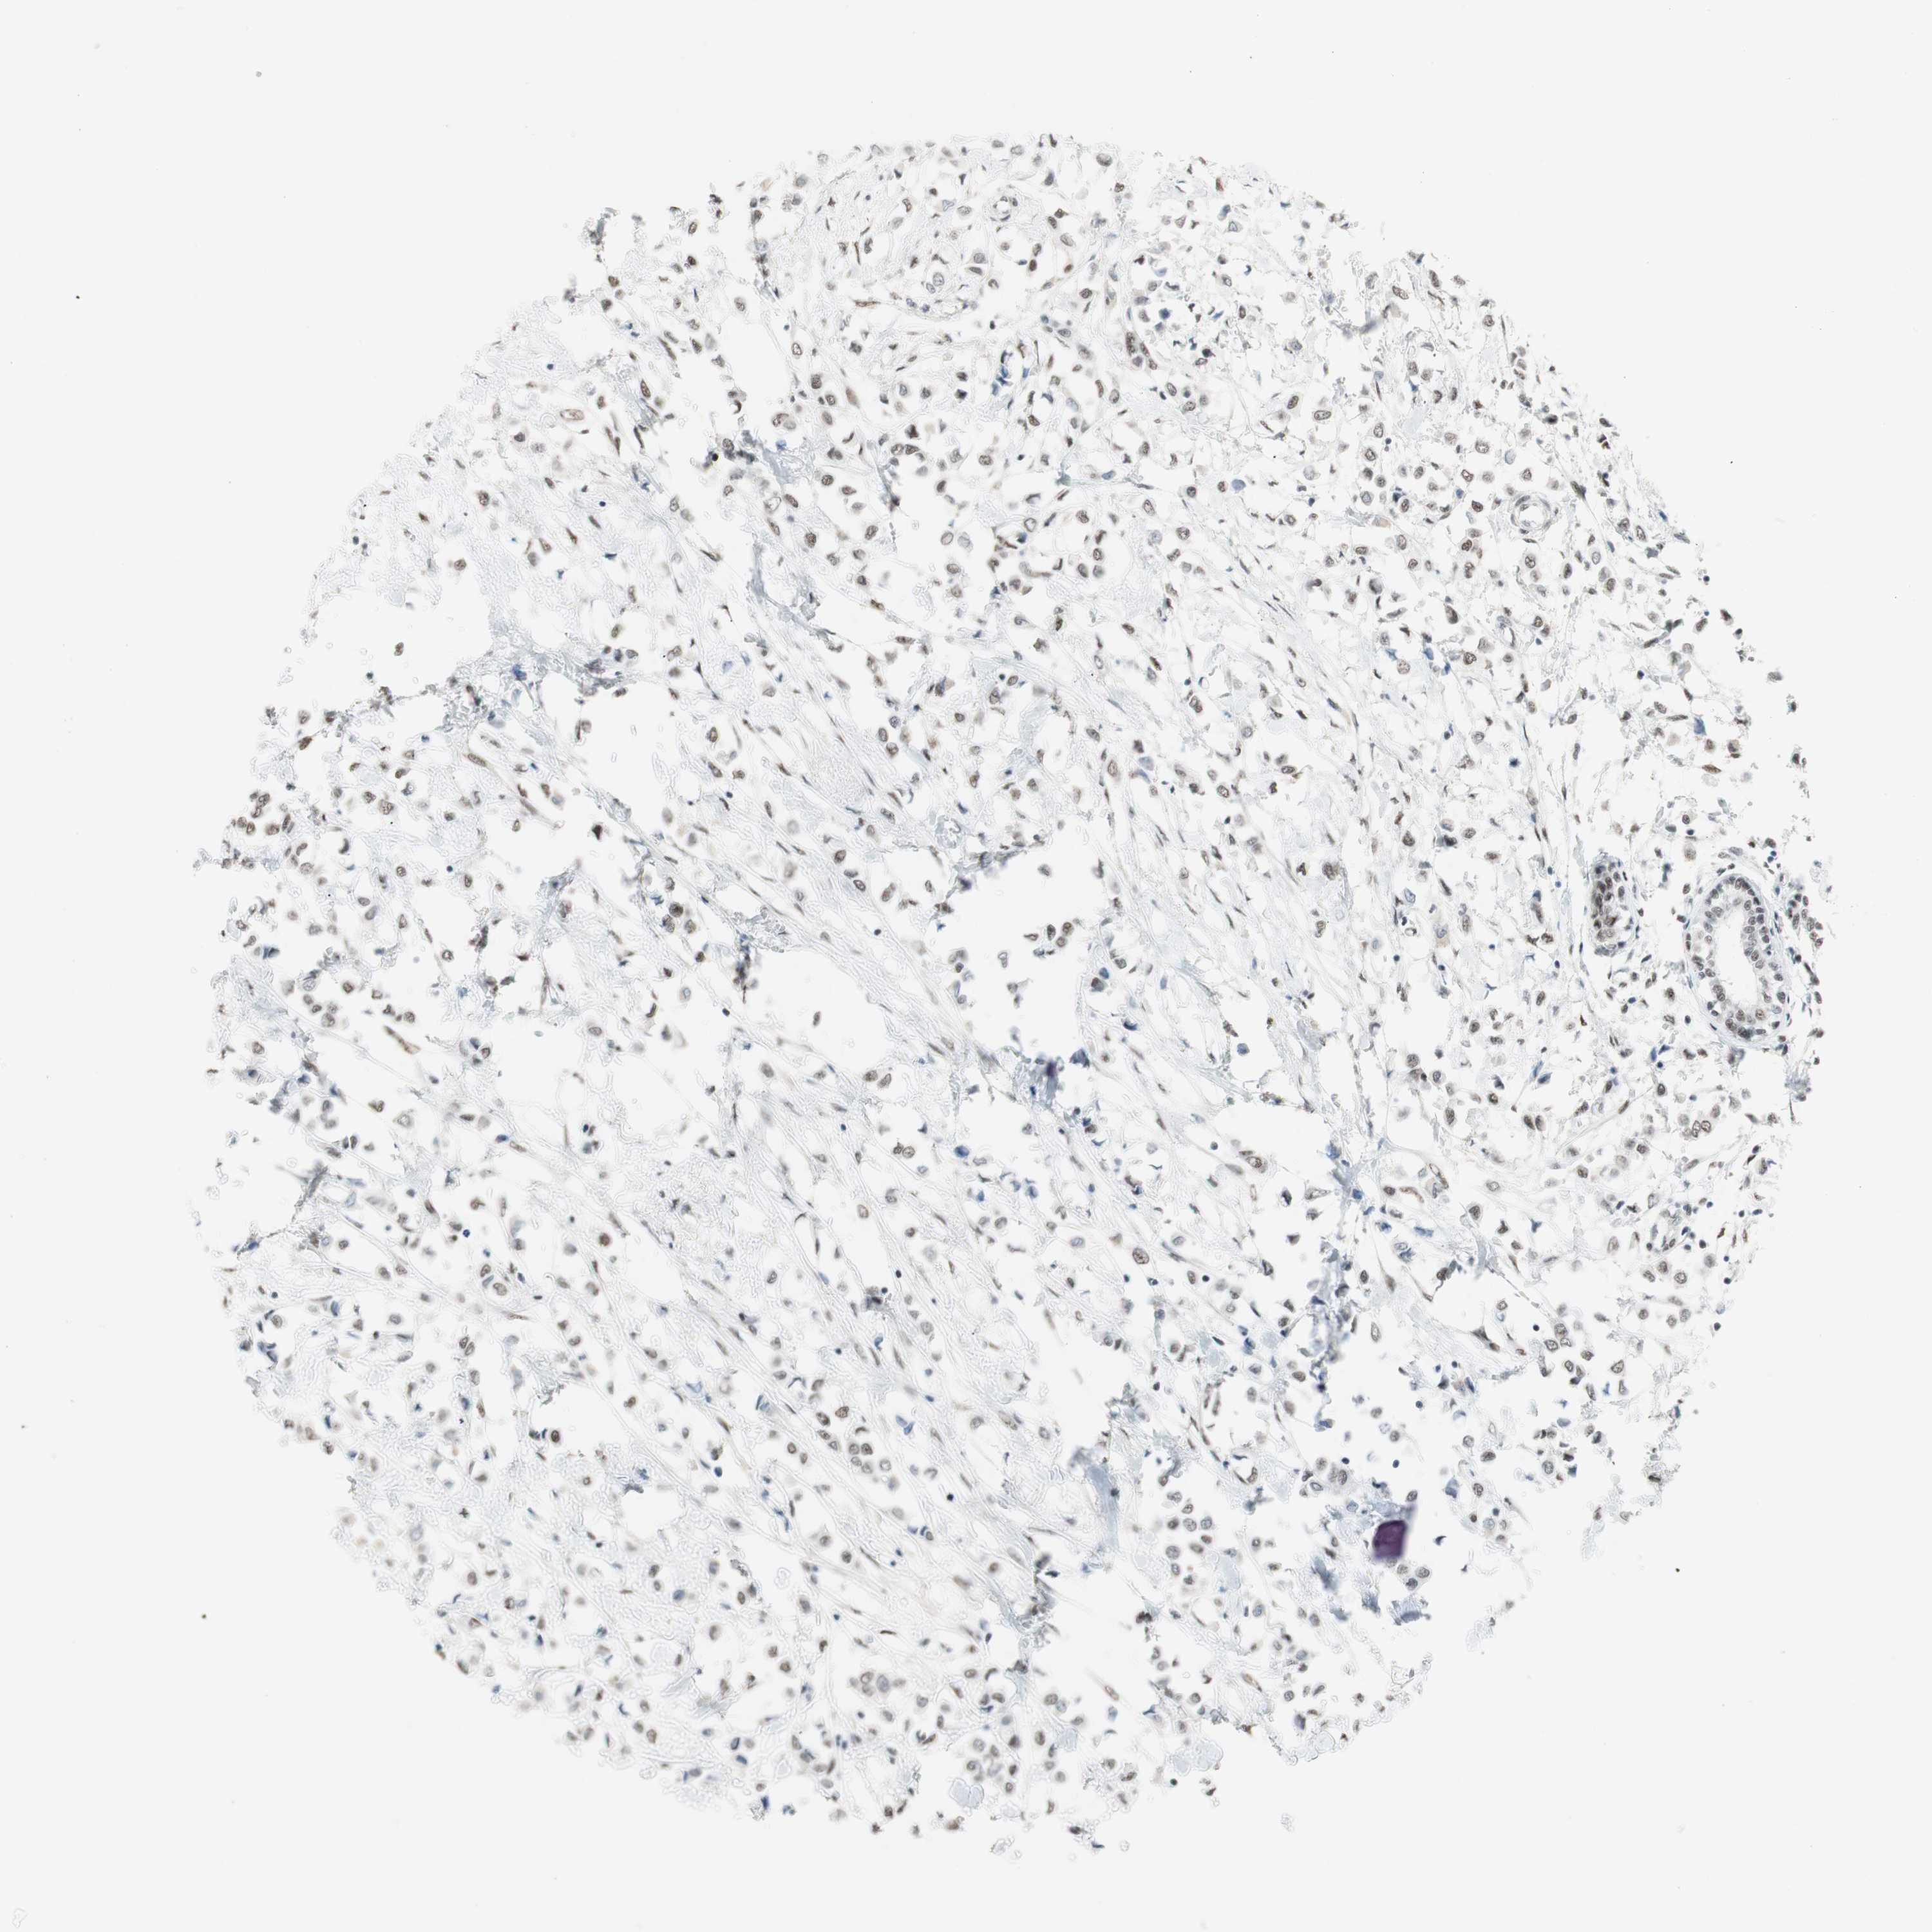

CANCER BREAST CANCER Show tissue menu

BRCA TCGA BRCA VALIDATION PROTEIN EXPRESSION